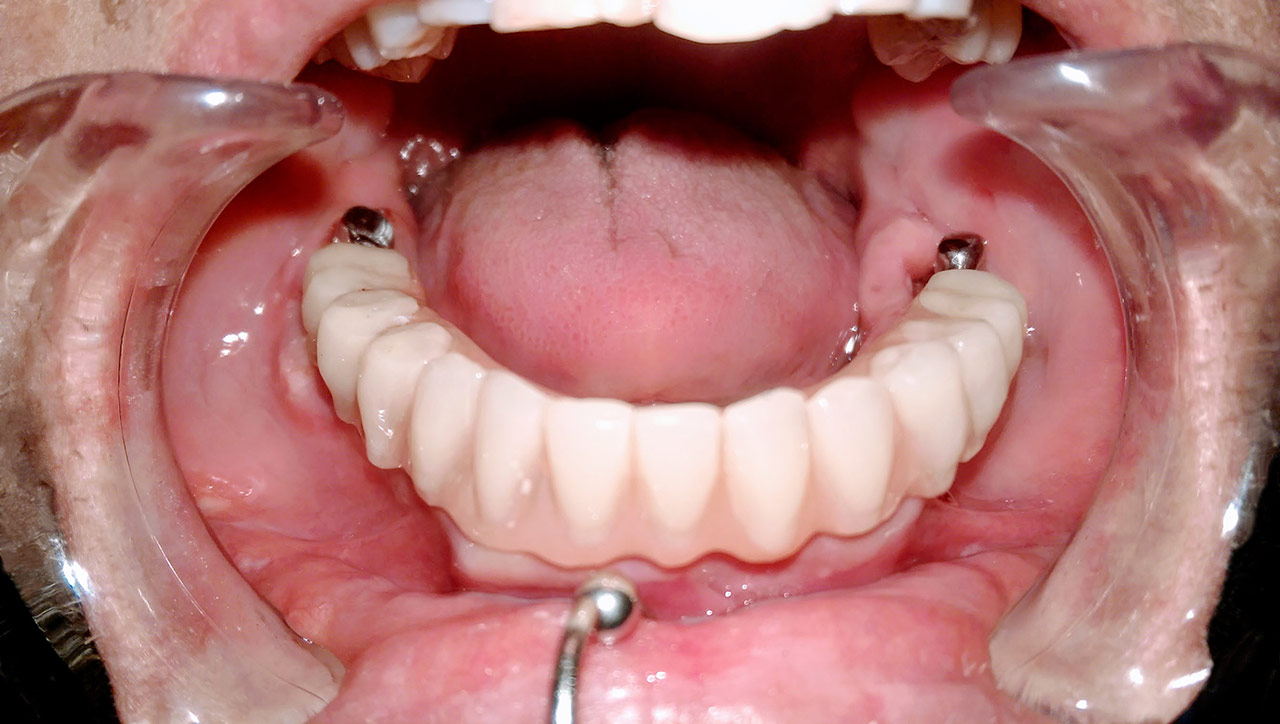

Alsó állcsont teljes rehabilitációja 72 óra alatt

Alsó állcsont teljes rehabilitációja 72 óra alatt, azonnal terhelhető implantátumokkal súlyos paradontitisben szenvedő dohányzó páciens esetében. Az alsó állcsont fogai mind mozogtak az előrehaladott fogágypusztulás miatt.

A fogakat eltávolítottuk, a gyulladt, fertőzött csontot kitakarítottuk, kifertőtlenítettük, majd azonnal implantáltunk.

Svájci, IHDE márkájú, azonnal terhelhető implantátumokat helyzetünk be, és ezekre harmadnapra rögzített, hosszútávú, fémvázas, esztétikus műanyaggal leplezett hidat ragasztottunk be.

Ezt az ideiglenes hidat a sebek gyógyulása miatt használjuk, de tartóssága miatt véglegesként is használható.

A legtöbb esetben, ahogy itt is, 6 hónap múlva porcelán hídra cseréljük, a teljes gyógyulás után.